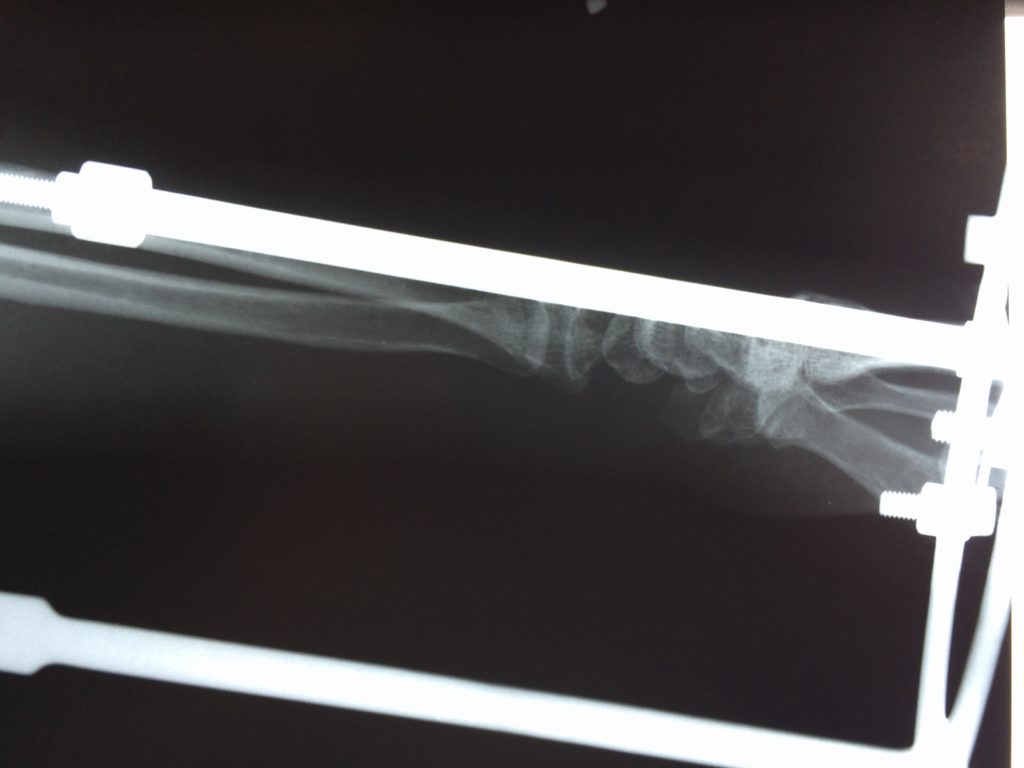

Операция - открытая репозиция, остеосинтез лучевой кости пластиной с костной ксенопластикой материалом "Остеоматрикс". На контрольных снимках в три месяца имеется консолидация перелома, миграции фиксатора нет, имеется остеоинтеграция ксенопластического материала.

Отдаленные результаты через 3 (три) месяца: